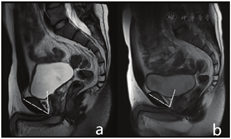

(8)耻骨直肠肌厚度(puborectal muscle thickness,PRM thickness):横轴位T2WI图像上PRM显示为经耻骨联合下缘水平肛管直肠交接处后方相对较厚的"U"形肌肉,最宽处内侧缘至外侧缘垂直走行长轴的距离即为PRM厚度(图4a、图4c)。

a、b:男性,25岁,横轴位T2WI图像上显示双侧PRM走行对称,信号均匀,左侧厚约5.59 mm,右侧厚约6.27 mm;冠状位T2WI图像上显示双侧ICM走行对称,信号均匀,左侧厚约4.52 mm,右侧厚约4.95 mm c、d:女性,24岁,横轴位T2WI图像上显示双侧PRM走行对称,信号均匀,左侧厚约7.47 mm,右侧厚约5.89 mm;冠状位T2WI图像上显示双侧ICM走行对称,信号均匀,左侧厚约5.57 mm,右侧厚约4.68 mm

a, b: Male, 25 years old, axial T2WI image showed bilateral PRM with symmetrical walking and uniform signal, with thickness of about 5.59 mm on the left and about 6.27mm on the right; coronal T2WI image showed bilateral ICM with symmetrical walking and uniform signal, with thickness of about 4.52mm on the left and 4.95mm on the right; c, d: Female, 24 years old, axial T2WI images showed bilateral PRM with symmetrical walking and uniform signal, with thickness of 7.47 mm on the left and about 5.89mm on the right; coronal T2WI image showed bilateral ICM with symmetrical walking and uniform signal, with thickness of about 5.57mm on the left and 4.68mm on the right.

(9)髂尾肌(iliococcygeal muscle thickness,ICM thickness)厚度:冠状位T2WI图像上ICM起自肛提肌腱弓,并向上凸起呈穹窿状,止于坐骨棘水平,肌肉最宽处上缘至下缘垂直走行的距离即为ICM厚度(图4b、图4d)。